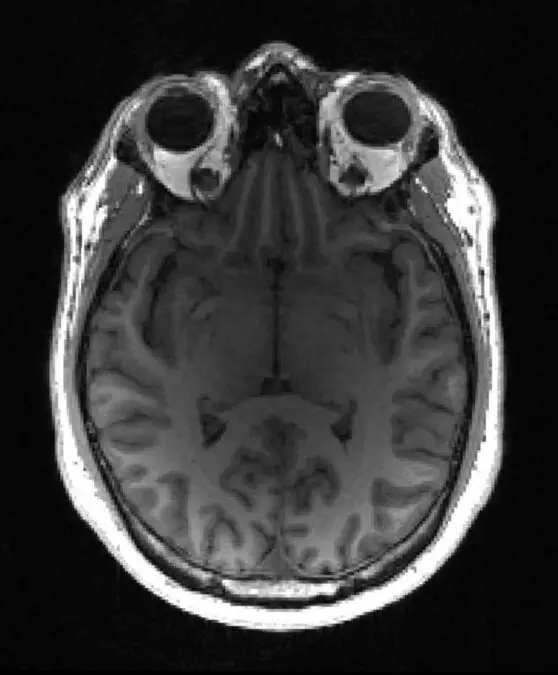

A team led by Professor Zoe Kourtzi at the University of Cambridge and The Alan Turing Institute has developed machine learning tools that can detect dementia in patients at a very early stage. Using brain scans from patients who went on to develop Alzheimer’s, their machine learning algorithm learned to spot structural changes in the brain. When combined with the results from standard memory tests, the algorithm was able to provide a prognostic score – that is, the likelihood of the individual having Alzheimer’s disease.

Professor Kourtzi, from Cambridge’s Department of Psychology, said: “We have trained machine learning algorithms to spot very early signs of dementia just by looking for patterns of grey matter loss – essentially, wearing away – in the brain. When we combine this with standard memory tests, we can predict whether an individual will show slower or faster decline in their cognition.

Although the algorithm has been optimized to look for signs of Alzheimer’s disease, Professor Kourtzi and colleagues are now training it to recognize different forms of dementia, each of which has its own characteristic pattern of volume loss.

Dennis underwent an MRI scan and later that same day he and Penny received the news that his results were consistent with early onset of Alzheimer’s disease. Dennis will begin taking medication to help treat the symptoms of Alzheimer’s disease.